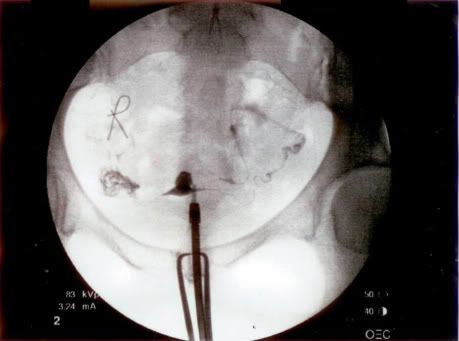

My Uterus Landed On The Moon

Yes, that is my uterus. Who knew it was so little? It's the dark sort of triangular blob in the middle. The jellyfish/spaghetti to either side are the fallopian tubes. Don't worry. The shy one all curled up is OK. They do that sometimes, I guess.

I passed my HSG or Hysterosalpingogram test. The test wasn't bad -- just a little cramping. If you want more details on the test or to see what an abnormal test might look like, this site is great.

So, what's next? More waiting. Next month I will take another round of Clomid and plan to have an IUI done. Although looking at the low success rates for the IUI procedure I'm ready to break out the big guns. In trying to find a bright spot in all of this, I am thankful I get a month break from the hot flashes.

I will try to get another post up soon so you don't have to stare at my insides. I know CP is thrilled about that :).